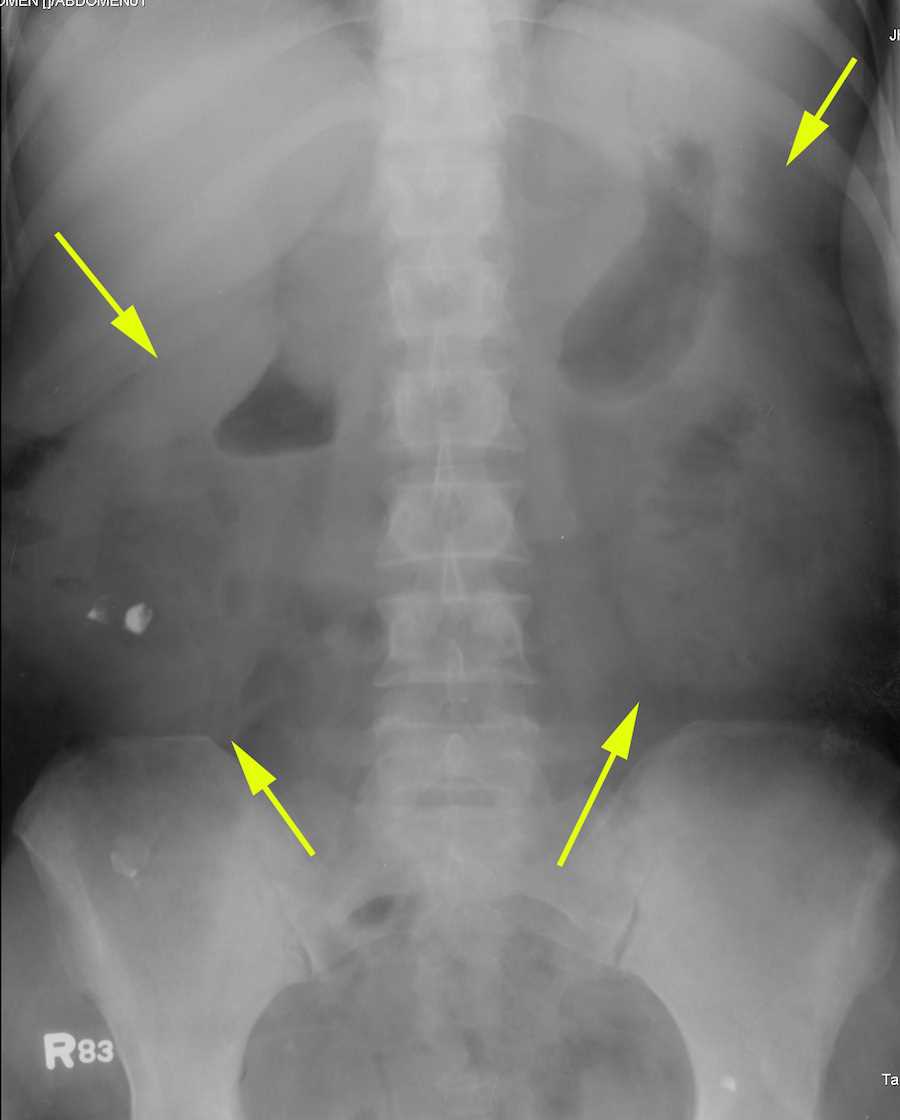

Cureus Horseshoe Kidney With a Documented Giant Calculi A Case Report Can Chest X-Ray Show Kidney Problems Kidney failure (kf) refers to a progressive decline in glomerular filtration rate to below 15 ml/min per 1.73 m 2, necessitating renal replacement therapy with dialysis or renal transplant. Our doctors use chest x. This case emphasises the importance of reviewing the. This study aimed to investigate whether. The tests available for diagnosing kidney diseases. Multimodality imaging plays a crucial. Can Chest X-Ray Show Kidney Problems.